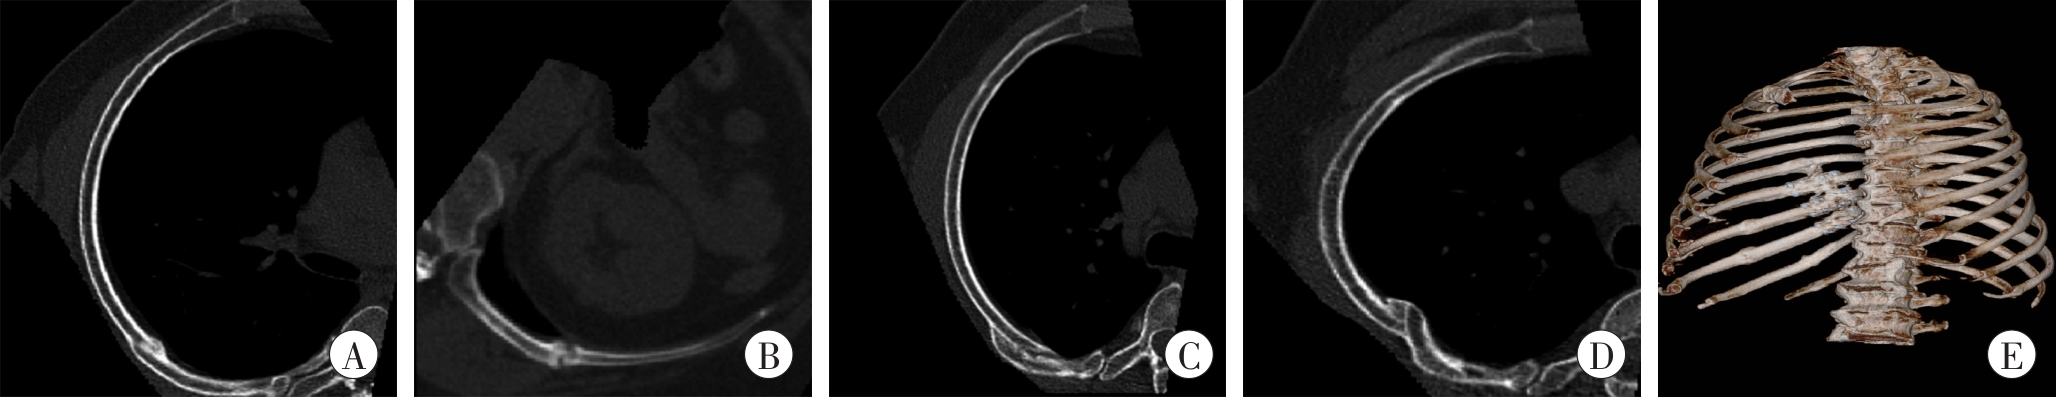

| 图1 不同类型的肋骨骨折畸形愈合 A:断端错合1/3以上(CPR图像);B:断端分离(CPR图像);C:断端重叠(CPR图像);D:断端成角(CPR图像);E:骨桥形成(VR图像)。  |

| Fig. 1 Different types of rib fracture malunion |